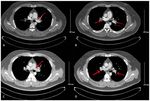

better outcomes in certain cases. Thrombolytic therapy using and high D‑dimer levels, computed tomography pulmonary

recombinant tissue‑type plasminogen activator, streptokinase angiography (CTPA) was performed to confirm the diagnosis,

or urokinase have been shown to result in faster improvements which showed intraluminal filling defects representing throm-

in pulmonary obstruction (98) with the associated significant boses in the bilateral pulmonary artery trunk and branches

reductions in the risk of hemodynamic decompensation or (Fig. 1A and B). Nephrotic syndrome (NS) due to minimal

collapse, despite an increased risk of severe extracranial and change disease and PE were diagnosed by renal biopsy and

intracranial bleeding (99). Percutaneous catheter‑directed CTPA, respectively. The patient therefore received oral

treatment and endovascular thrombolysis by means of cath- prednisone treatment. PE risk stratification was performed to

eter are also important alternatives for PE treatment (100). determine the simplified PE severity index (sPESI) and guide

Vena cava filters can mechanically prevent venous clots from treatment strategy. His initial stratification was determined as

reaching the pulmonary circulation. Most filters in current use ‘not high‑risk’ with a sPESI of 0. Therefore, anticoagulation

are inserted percutaneously and can be retrieved after several therapy with 15 mg rivaroxaban twice daily was initiated. The

weeks or months, or left in place long‑term in patients with patient was discharged from the hospital after 10 days. After

contraindications to anticoagulant treatment or recurrent PE 3 weeks, the rivaroxaban dose was reduced to 20 mg once daily

despite adequate anticoagulation (101). and prednisone was continued. At follow‑up 90 days after

discharge, the symptoms had disappeared and the laboratory

8. Adverse effects or toxicity associated with rivaroxaban results, including those of plasma total protein and albumin,

24 h urine protein quantification, total cholesterol and LDL,

Despite fewer interactions which may cause unpredictable D‑dimer and arterial blood gas levels had nearly normalized

anticoagulation outcomes with rivaroxaban and other NOACs, (Table IV). Repeat CTPA yielded normal results after 90 days

every patient should be considered on a personalized basis, on rivaroxaban (Fig. 1C and D), following which the drug was

especially when a combination of interfering underlying discontinued.